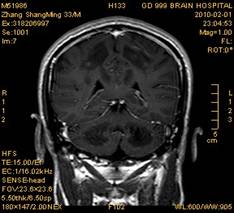

案例1 患者,男,33岁, 海洛因脑病的头颅MR。表现为双侧大脑后部皮层下白质、双侧内囊后肢、枕叶白质、胼胝体压部、中脑、桥脑、双侧小脑半球齿状核质及双侧桥臂多发对称性片状及斑片状长T1长T2异常信号影,FLAIR序列呈高信号,其中双侧内囊后肢表现为特异的“八字征”,双侧小脑半球齿状

核质表现为对称的“蝶翼征”,脑干病变呈“蟹钳征”及“中空征”。增强后双侧半卵圆中心、双侧枕叶白质及双侧小脑半球病变内或边缘中度强化影。给予患者抗炎、脱水、疏通血管及营养神经等药物治疗,一个月后痊愈出院。